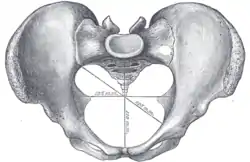

Male type pelvis | |

Female type pelvis | |

The principal differences between male and female true and false pelvis include:

- The female pelvis is larger and broader than the male pelvis which is taller, narrower, and more compact.[10] The female pelvis is lighter and thinner than the male pelvis.[11]

- The female inlet is larger and oval in shape, while the male sacral promontory projects further (i.e. the male inlet is more heart-shaped).[10]

- The sides of the male pelvis converge from the inlet to the outlet, whereas the sides of the female pelvis are wider apart.[12]

- The angle between the inferior pubic rami is acute (70 degrees) in men, but obtuse (90–100 degrees) in women. Accordingly, the angle is called subpubic angle in men and pubic arch in women.[10] Additionally, the bones forming the angle/arch are more concave in females but straight in males.[13]

- The distance between the ischia bones is small in males, making the outlet narrow, but large in females, who have a relatively large outlet. The ischial spines and tuberosities are heavier and project farther into the pelvic cavity in males. The greater sciatic notch is wider in females.[13]

- The iliac crests are higher and more pronounced in males, making the male false pelvis deeper and more narrow than in females.[13]

- The male sacrum is long, narrow, more straight, and has a pronounced sacral promontory. The female sacrum is shorter, wider, more curved posteriorly, and has a less pronounced promontory.[13]

- The acetabula are wider apart in females than in males.[13] In males, the acetabulum faces more laterally, while it faces more anteriorly in females. Consequently, when males walk the leg can move forwards and backwards in a single plane. In females, the leg must swing forward and inward, from where the pivoting head of the femur moves the leg back in another plane. This change in the angle of the femoral head gives the female gait its characteristic (i.e. swinging of hips).[14]